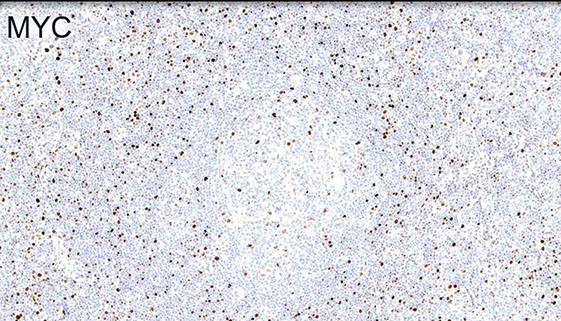

MYC is often increased usually in proliferation centers (sometimes with inc Ki67)

MYC more strongly positive in proliferation center-like areas